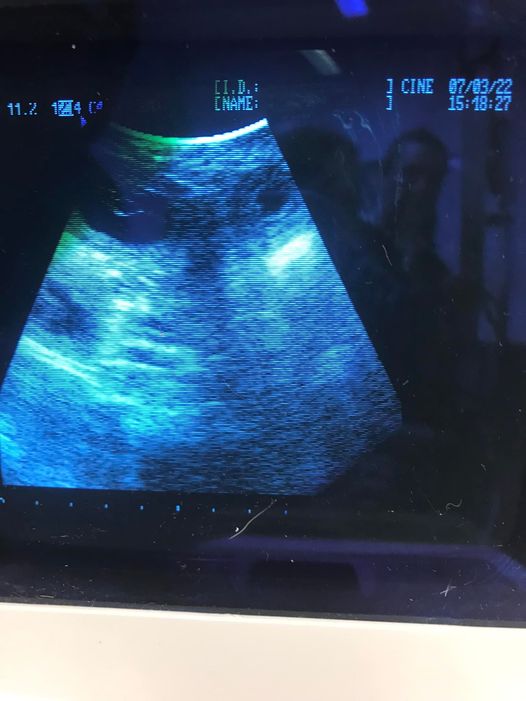

Päivittämättä jäi viimeiset tiineysviikot. Tässä siis kuva viikolta 8.

Kävimme 7.3., juuri 30 tiineysvuorokaudella varmistamassa tiineyden Paimion Pikkupedossa. Aija on odotuksien mukaisesti tukevasti tiineenä. Se asustelee meillä koko tiineysajan, jotta paikat on tuttuja sitten synnytyksen koittaessa. :) Pentueen isä on meidän oma Morkkiksemme. Tällä hetkellä varauslista on aika piukassa, emmekä ota lisävarauksia.